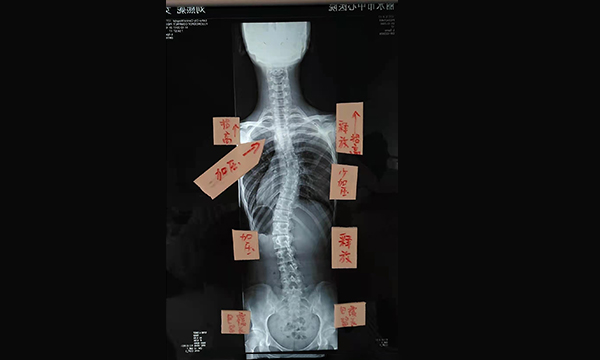

脊柱畸形對青少年身心健康的危害性極大

由于脊柱側彎病人不痛不癢,毫無癥狀,而且又是小孩···

什么是脊柱畸形和脊柱側彎

通俗的說,脊柱畸形就是人的脊柱長歪了,它包括多種類型,如果左右方向長歪了,就叫脊柱側凸

如何早期發(fā)現(xiàn)脊柱畸形和脊柱側彎

家長們多花一些精力仔細觀察孩子可早期發(fā)現(xiàn)脊柱畸形